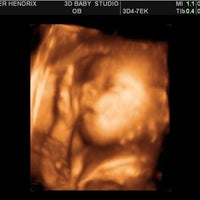

This video contains Sooe babys 34 Weekss 3D4D ultrasound session.

3d baby ultrasound charlotte nc. 3d 4d ultrasound charlotte nc Video Prenatal 3D 4D Ultrasound offers the best and the most stunning ultrasound baby images perfect for gender determination and appreciating the beauty that is the life of your baby. Russell Our 4d ultrasound baby showers are so much fun for expecting moms friends and family. The ultrasound room easily fit 9 people and could fit more and had two tv screens for viewing with up to date equipment and decor.

We Specialize in 4D Ultrasound 3D Ultrasound 3D 4D Prenatal Ultrasounds and Elective Ultrasounds. We use cutting edge ultrasound technology to bring images of your unborn baby to life and our sonographer Roxanne Cortes is a registered diagnostic medical sonographer with 20 years of OBGYN. Baby Flix 3D 4D ULTRASOUND CHARLOTTE NC Video Prenatal 3D 4D Ultrasound offers the best and the most stunning ultrasound baby images perfect for gender determination and appreciating the beauty that is the life of your baby.